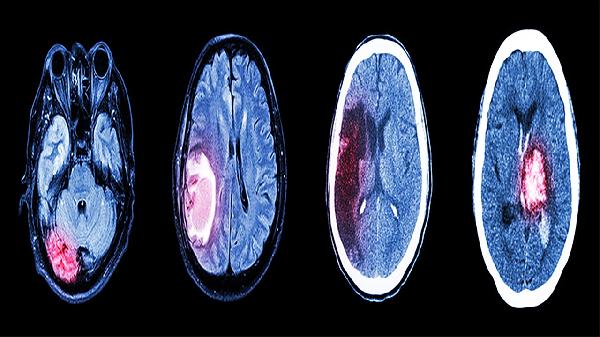

2、材料选择

儿童颅骨修补材料需具备生物相容性、可塑性和生长适应性。常用材料包括钛网、聚醚醚酮和自体骨。钛网强度高但可能影响影像学检查。聚醚醚酮可定制且不影响生长发育。自体骨移植兼容性好但存在吸收风险。需根据缺损部位、面积及患儿年龄选择最适材料。